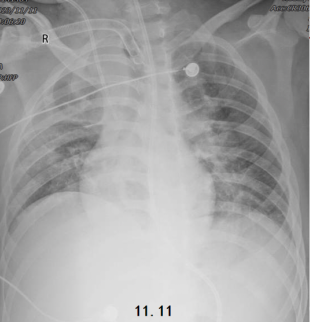

治疗1周后,患者胸部X线片较入院时改善,病变吸收明显(图5)体温也有所下降(图6)

图片

图5  患者胸部X线片

由于患者出现了气压伤,因此加大了镇痛镇静力度,并且予适当的肌松剂,考虑患者痰液排出困难,进行了气管切开,加强痰液引流。患者氧合有所改善,维持在100~200 mmHg,PaCO维持在50 mmHg以内,分钟通气量为6~7 L/min,仍有发热(图10)。11月11日(气管切开后,PEEP下调)胸部X线片可见皮下气肿和气压伤好转,但肺容积较前减少(图11)

图11  患者11月11日胸片